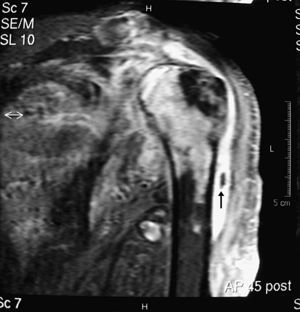

En la exploración destacaba una temperatura axilar de 39,1°C; tumefacción y derrame fluctuante en el hombro izquierdo con restricción activa y pasiva de todos sus movimientos, disminución de la sensibilidad dolorosa y térmica en el miembro superior izquierdo y moderada hiperreflexia en el miembro superior derecho. El resto de la exploración no mostró datos reseñables. En los análisis se objetivó elevación de la VSG (132mm/1.a h), de la proteína C reactiva (217mg/l), anemia normocrómica normocítica (Hb: 109g/l), leucocitosis (12,7×109/mm3; 89% neutrófilos) y trombocitosis (435×109/l). Los siguientes parámetros fueron normales o negativos: glucosa, urea, creatinina, colesterol, lacticodehidrogenasa, transaminasas, creatincinasa, aldolasa, sodio, potasio, calcio, fósforo, fosfatasa alcalina, proteinograma, TSH, T4L, dosificación de inmunoglobulinas, factor reumatoide y anticuerpos antinucleares. Las radiografías del hombro izquierdo mostraron disminución del espacio subacromial, irregularidad del contorno de la cabeza humeral, osteopenia difusa y aumento de volumen y densidad de partes blandas. Además, la ecografía objetivó abundante derrame articular con cuerpos libres, comunicación de la bolsa subacromial con la cavidad glenohumeral, rotura completa de los tendones supraespinoso, infraespinoso y subescapular, así como subluxación bicipital. La RM confirmó estos hallazgos y objetivó edema de partes blandas periarticulares, de la cabeza humeral y de la cavidad glenoidea (fig. 1). Las gammagrafías con Tc99m y Ga67 mostraron hipercaptación del trazador en el hombro izquierdo. El estudio neurofisiológico (EMG, ENG y los potenciales evocados somatosensoriales) pusieron en evidencia una lesión neurogénica denervativa en los miotomas dependientes de C6, C7 y D1 de intensidad moderada y hallazgos compatibles con afectación de la vía sensitiva.